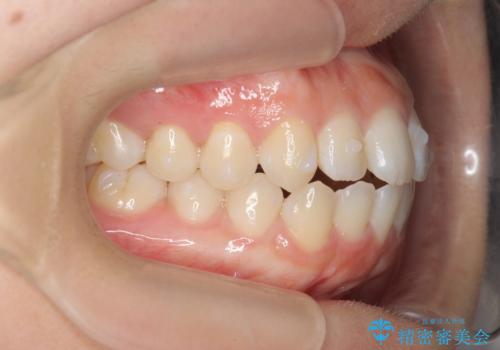

前歯のすれ違い インビザラインで行うマウスピース矯正

- 前歯のガタつき、でこぼこ、前後が逆になっている噛み合わせの改善を求めて来院されました。

治療の装置が目立たず歯ブラシのしやすいマウスピース矯正インビザラインでの治療を計画します。

20時間/日の装用時間をしっかりと守っていただき、きれいな歯並びを手に入れることができました。